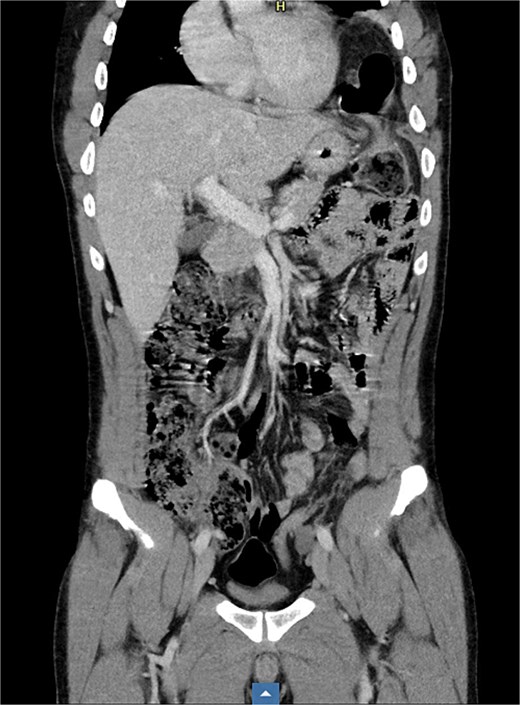

The contrast-enhanced computed tomography (CT) scan revealed a left 2-cm-large diaphragmatic hernia at the level of the diaphragmatic dome, with herniation of the transverse colon and omentum (Fig. 2). There were no radiological signs of bowel obstruction.